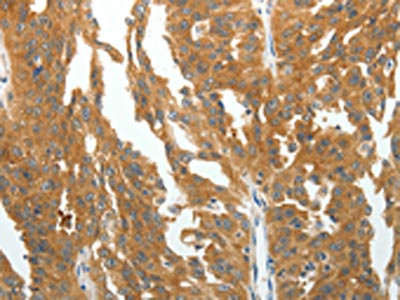

The image on the left is immunohistochemistry of paraffin-embedded Human colon cancer tissue using CSB-PA826561(RGS2 Antibody) at dilution 1/40, on the right is treated with fusion protein. (Original magnification: ×200)

The image on the left is immunohistochemistry of paraffin-embedded Human ovarian cancer tissue using CSB-PA826561(RGS2 Antibody) at dilution 1/40, on the right is treated with fusion protein. (Original magnification: ×200)